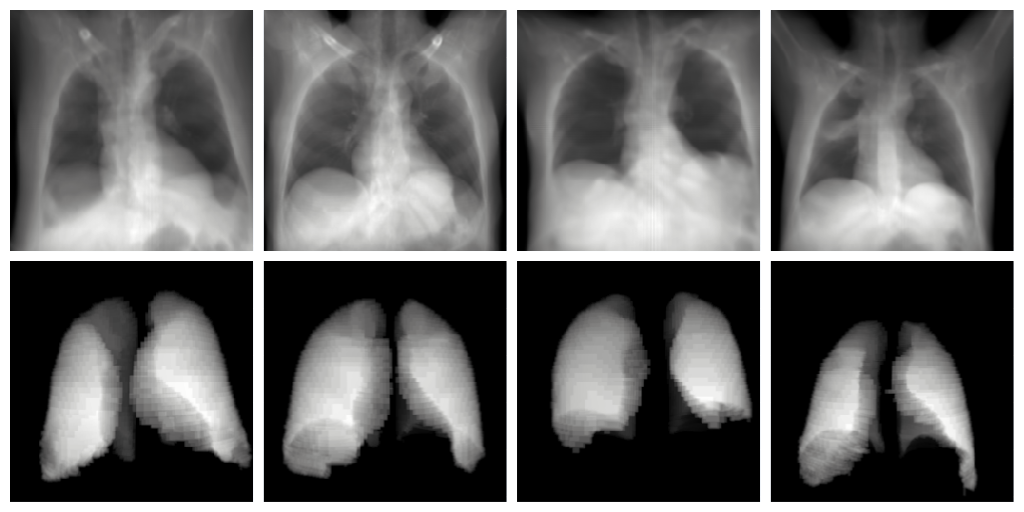

In order to show the advantages of NeRP, we compare its performance against DRRs on Lung segmentation of Chest XR in the scenario of lacking the training data entirely, only test on given manual sets as discussed. To make a fair assessment, we set the same viewpoint-generated VRRs from NeRP and DRRs. The only difference between them is that our radiance is learnable while DRRs have fixed HU-based and constant . Fig. 3 indicates some VRR samples generated by NeRP that have been used for training a vanilla UNet to perform pixel-based lung segmentation problems. As can be seen in Table 3, using our method can outperform a DRR-based dataset up to 5% on the Dice Score [19] metrics. This can be explained that the XR images produced by NeRP are much typical than by DRRs, and hence require less overhead transfer compared to those direct DRR CT-generated samples.